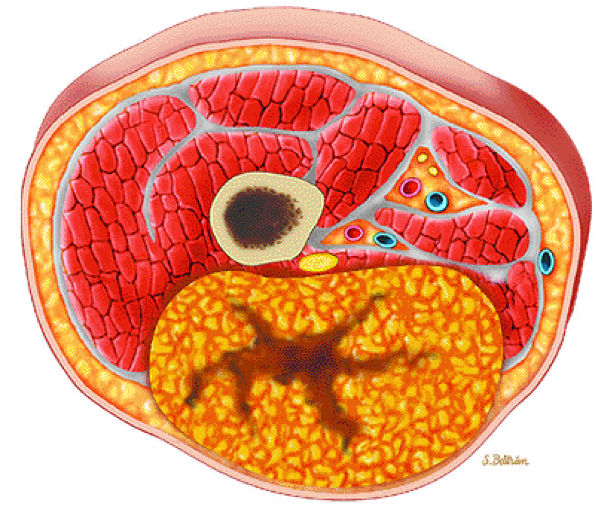

T1- and T2-weighted images (including fat-suppressed T2-weighted fast spin-echo or STIR sequences) in the axial plane provide the most important images in delineating the relationship of a tumor to adjacent neurovascular structures and compartments—essential information in preoperative limb-salvage planning.

MR imaging is accurate in determining the local extent of tumor and involvement of muscle compartments, joints, and neurovascular bundles.

Evaluation of intra- and extraosseous extent, joint invasion, neurovascular bundle involvement, skip metastases, and local adenopathy as well as distant metastases is important for accurate staging and subsequent therapy.